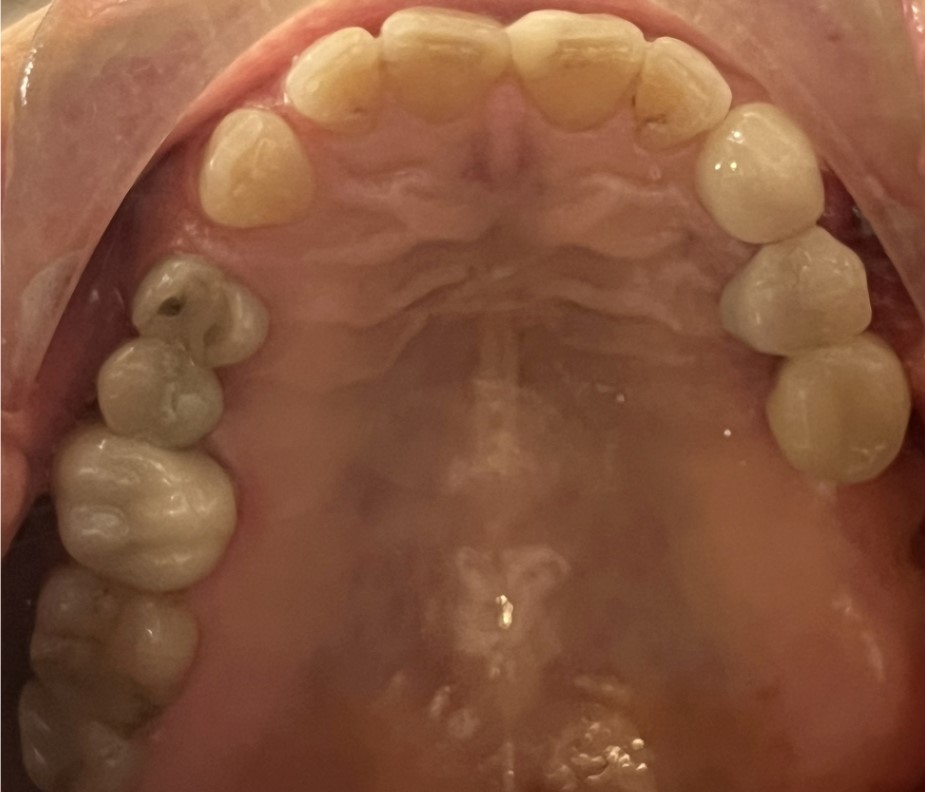

Dental implants can be used when:

- A single tooth is missing – Crowns

- Several teeth are missing – Bridges

- All teeth are missing – Bridges or dentures